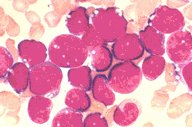

Acute lymphoblastic leukemia (L3)(Burkitt's),

high-oil mag, BMA

Acute lymphoblastic leukemia (L3). This high-oil

magnification view of a bone marrow aspirate

shows characteristics blasts of the L3 or Burkitt's

type. Cytoplasmic and nuclear vacuoles are seen.